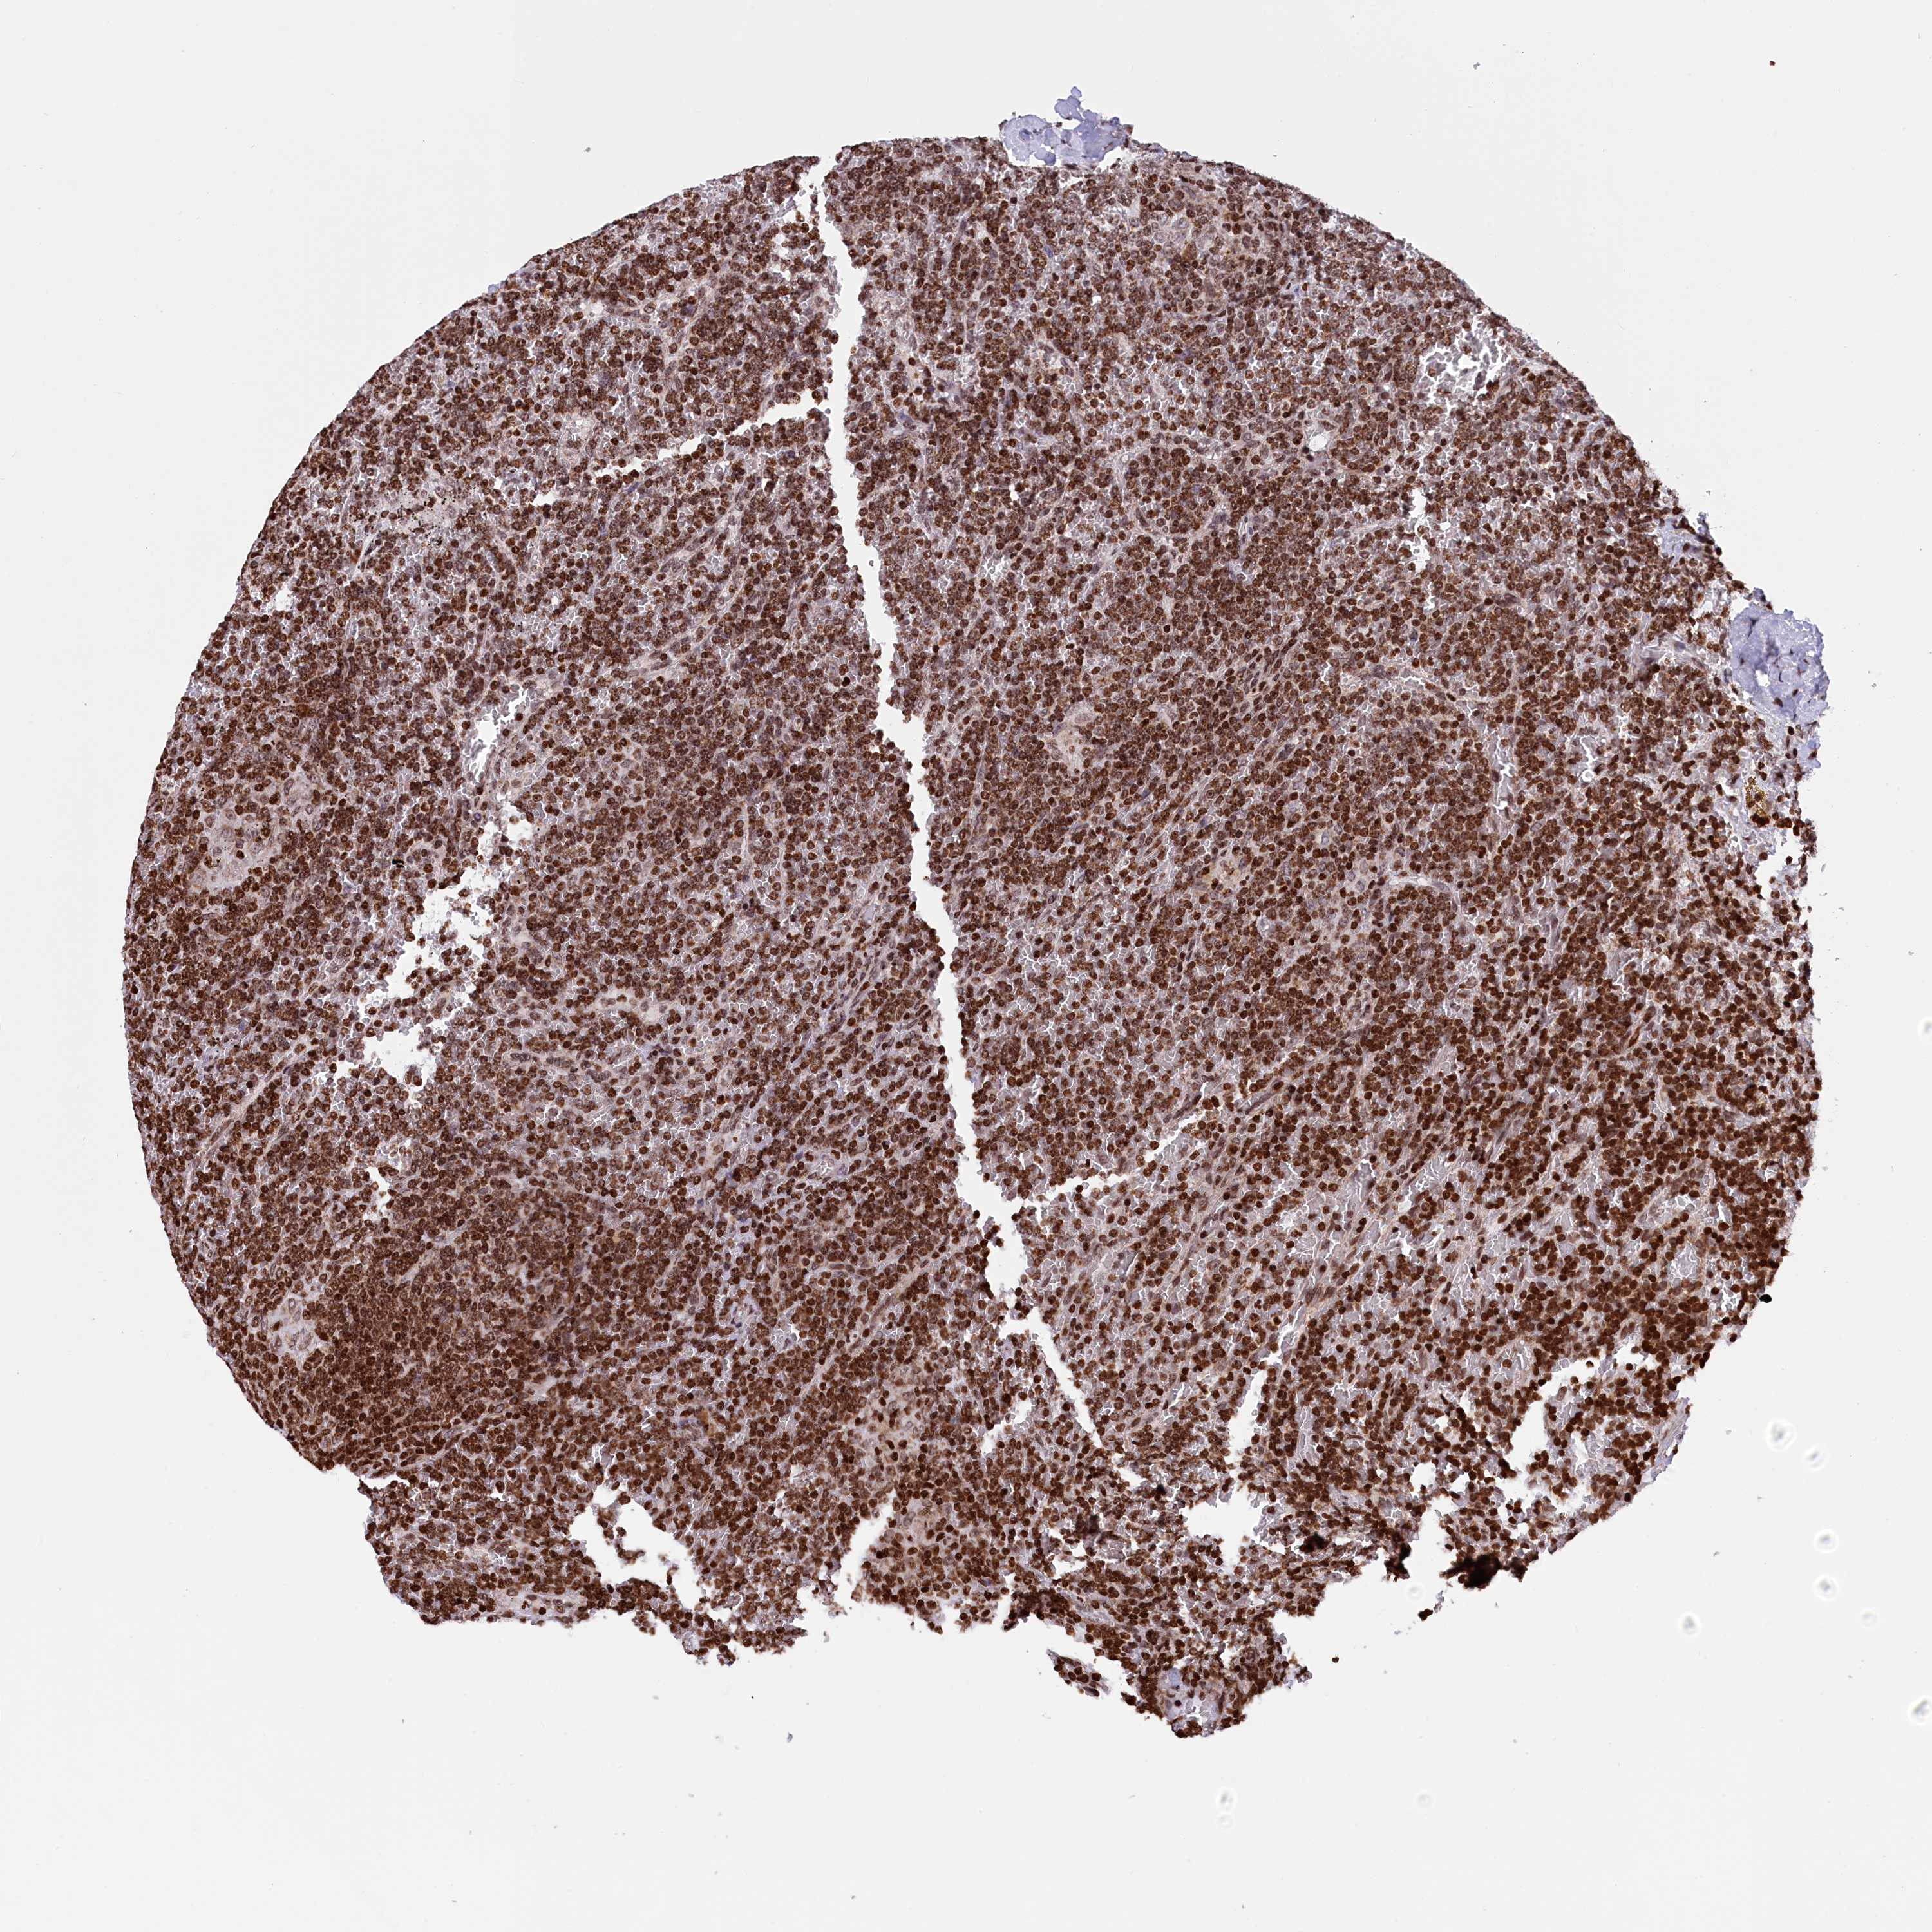

CANCER LYMPHOMA Show tissue menu

LYMPHOMA - Protein expressioni

A mouse-over function shows sample information and annotation data. Click on an image to view it in a full screen mode. Samples can be filtered based on level of antibody staining by selecting one or several of the following categories: high, medium, low and not detected. The assay and annotation is described here.

Each image is clickable and will lead to virtual microscopy that enables deeper exploration of all samples and also displays staining intensity scores, fraction scores and subcellular localization as well as patient and tissue information for each sample.

Antibody HPA041858

Staining

High

Intensity

Strong

Quantity

>75%

Location

Nuclear

Hodgkin's disease, NOS

Malignant lymphoma, non-Hodgkin's type, High grade

Malignant lymphoma, non-Hodgkin's type, Low grade